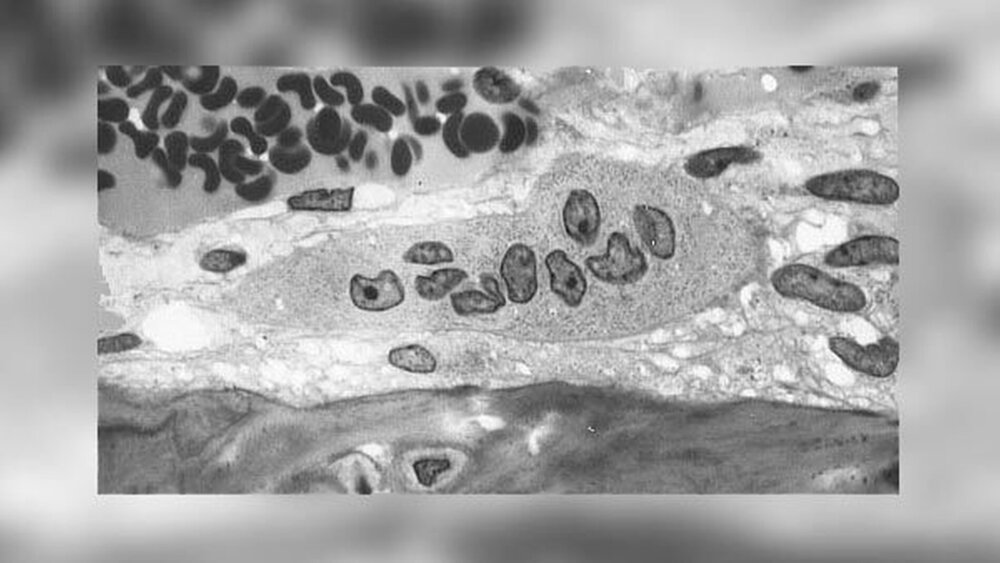

Die histologische Auswertung der Knochenproben ergab signifikant weniger Knochenfläche in der Patienten-Gruppe, die Traubenkernextrakte einnahmen, dafür mehr lockeres Bindegewebe und mehr Blutplättchen im Vergleich zu der Gruppe mit den Grapefruitextrakten und den Kontrollen.

Zusammenfassend zeigte die Studiengruppe mit den Traubenkernextrakt-Nahrungsergänzungsmitteln weniger dichten und mehr unreifen Knochen in ihren Knochenproben, dazu mehr Thrombozyten und fibröses Gewebe. Traubenkernextrakt scheint die Menge an neugebildetem Knochen im Unterschied zu Grapefruitextrakten und den Kontroll-Proben zu reduzieren, während Grapefruitextrakt die Entzündungsbotenstoffe herunterreguliert und mehr reifen Knochen entstehen lässt.